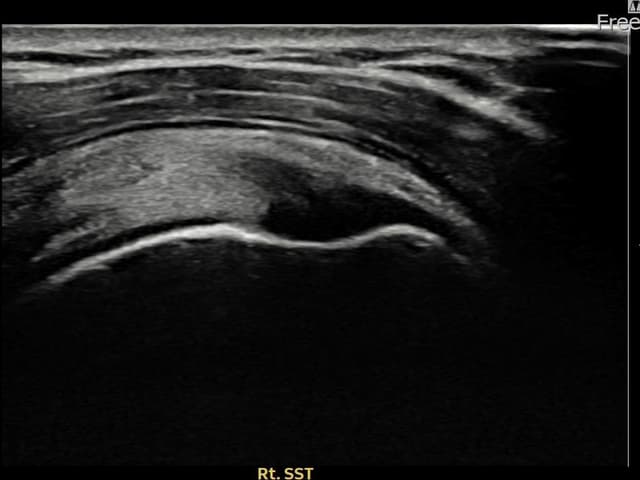

[経過期間: 23.07.31~23.09.27]

[縫縮術] 超音波検査にて左 棘上筋腱 부착부 광범위 部分断裂(13mm × 5mm (腱厚の約65%欠損))を確認。縫縮術施行後、腱の連続性が回復し、日常生活に復帰されました。